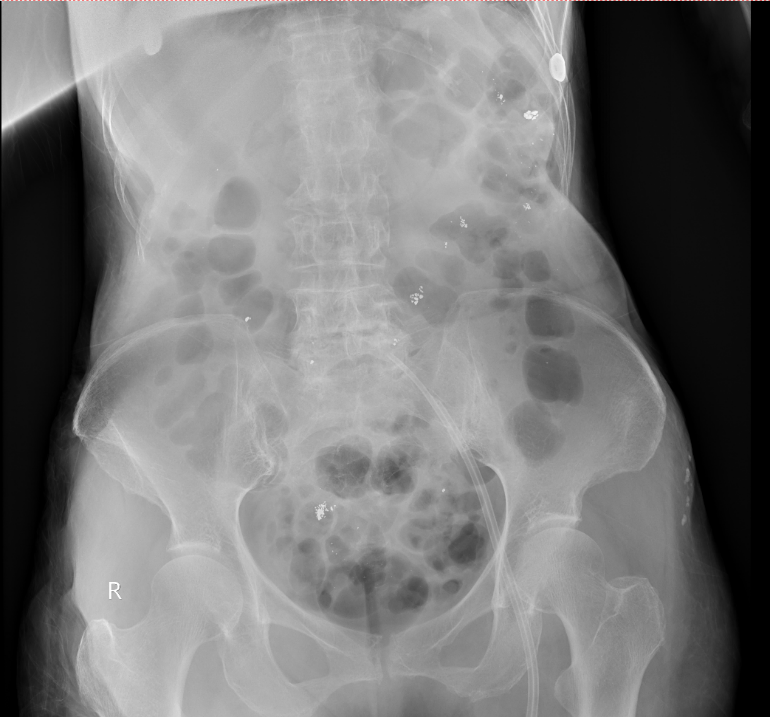

d2.jpg 腹平片可以看到患者消化道内残留大量汞

入院当天,姜阿婆尿汞浓度高达73465.47μg/L(肌酐校正),比正常值高1万8千多倍;反映肾功能的肌酐清除率仅有6.21ml/min,出现无尿,提示已存在肾功能衰竭;转氨酶、心肌酶升高,肝脏、心肌均出现了不同程度的损害。